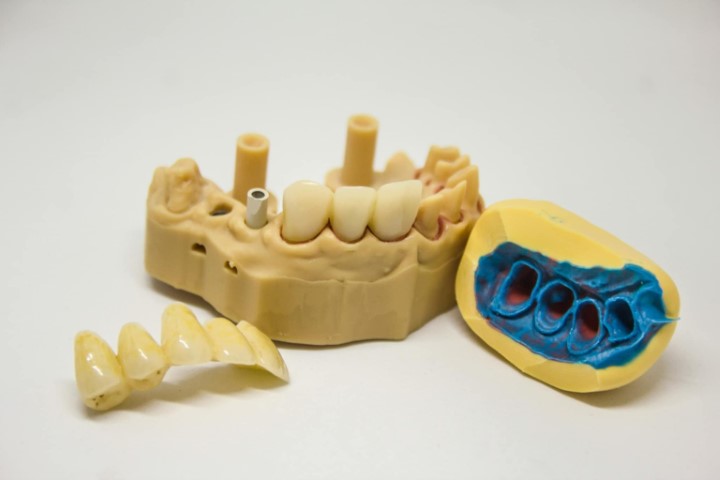

Διάγνωση και σχεδιασμός – ψηφιακές ακτινογραφίες και 3D απεικόνιση για τον ακριβή προγραμματισμό.

Αποκατάσταση με στεφάνη ή γέφυρα – ολοκληρώνεται η αισθητική και λειτουργική αποκατάσταση.

Χρήση σύγχρονου εξοπλισμού και ψηφιακής τεχνολογίας,